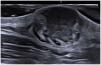

Ecográficamente, todos los casos mostraron una hipoecogenicidad superficial y 10 de ellos presentaron una hiperecogenicidad en la base. Un hallazgo frecuente fueron las proyecciones seudópodas (12/14; 85,7%) (fig. 1). La ecografía Doppler color mostró una hipervascularización en 12 casos (85,7%). En estos casos, el ultrasonido de alta resolución sugirió el diagnóstico, finalmente confirmándose con estudio histopatológico.

Hallazgos ecográficos de DFSP. Ultrasonido en escala de grises, visión longitudinal. Muestra imagen clásica de DFSP con masa ovalada, de bordes mal definidos, con banda hipoecoica en la dermis e hipodermis (marca blanca). En la base la lesión es hiperecoica con bordes conexos y proyecciones seudópodas (marcadores amarillos).

La ecografía permite la caracterización y diferenciación de masas de tejidos blandos superficiales3. Diago et al. encontraron 4 patrones de invasión ecográfica del DFSP, con una buena correlación histopatológica. El patrón más común (53,3%), igual que en nuestros casos, fue la presencia de masa hipoecoica oval con unas proyecciones seudópodas o digitiformes y áreas hiperecoicas posteriores (fig. 1) que se correlacionaban con la extensión de las células tumorales y fibroblastos dispersos en el tejido subcutáneo formando el patrón característico de panal de abejas. Cabe mencionar que las proyecciones digitiformes presentan un crecimiento asimétrico e impredecible, considerándose altamente indicativas o patognomónicas. Dichas estructuras se encontraron en la mayoría de nuestros casos (fig. 2). El segundo en frecuencia fue el patrón hipoecoico oval con unas proyecciones seudópodas pero sin las áreas hiperecoicas posteriores (20%), correlacionándose con la extensión a lo largo del septo subcutáneo. Por último, describieron un patrón mixto invasivo, pero sin proyecciones profundas (16,7%) o tumores hipoecoicos ovales dérmicos/subcutáneos (10%). La ecografía presenta una tasa de sensibilidad del 81,8% y especificidad del 100% para detectar invasión profunda, con un valor predictivo positivo del 83,3%, resaltando su importancia para evaluar extensión tumoral8.